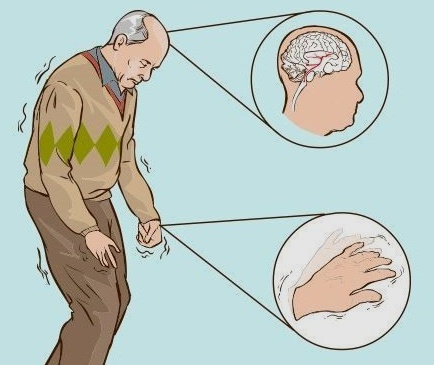

파킨슨병(약칭 PD)은 중뇌 흑질에서 도파민을 분비하는 신경세포(뉴런)가 서서히 소실돼

느린 운동, 근육 떨림과 강직, 자세 불안정 등으로 이어지는 대표적인 신경 퇴행 질환입니다.

세계적으로 파킨슨병 환자는 700만 명에서, 많게는 1천만 명에 이를 거로 추정 됩니다.